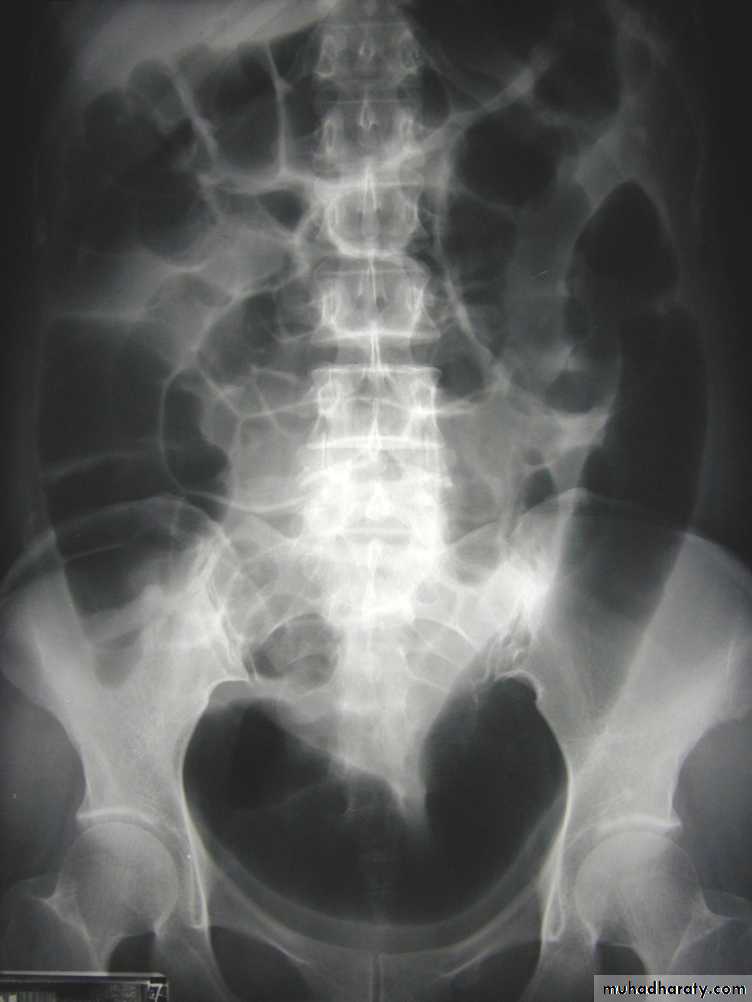

UC

The colon is distended with air

The descending & sigmoid colon are featureless (no haustral pattern)

•

Thumb printing

Radiological features of toxic megacolon :

• The colon (typically transverse colon) becomes dilated to at least 6 cm (usually greater). There is additional loss of haustral markings

• It is serious acute abdominal condition

• More in UC > CD